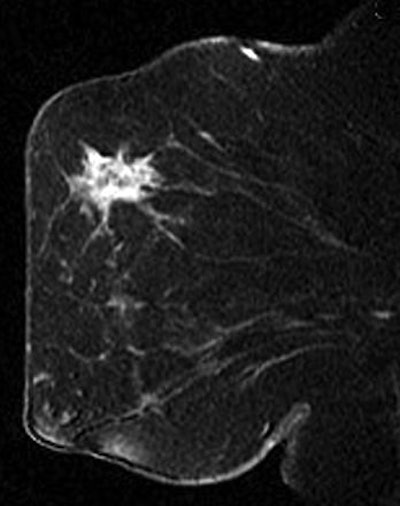

| A 41-year-old patient with invasive ductal carcinoma, grade III, studied while undergoing neoadjuvant chemotherapy treatment. MRI was performed using contrast-enhanced 3D fast gradient-recalled echo pulse sequence (TR/TE, 8/4.2; flip angle, 20°; 18-cm field-of-view, 2-mm slice thickness, 256 x 192 acquisition matrix). Patient presented with 71 cm3 (6.2-cm diameter) tumor and experienced increase in MRI tumor volume throughout treatment (28% overall increase). At surgery, 8 cm of residual disease and nine involved lymph nodes were identified. Patient experienced disease recurrence eight months after surgery. Maximum intensity projection (left) with corresponding tumor volume segmentation for representative sagittal slice (right) acquired before initiation of chemotherapy. Partridge SC, Gibbs JE, Lu Y, Esserman LJ, Tripathy D, Wolverton DS, Rugo HS, Hwang ES, Ewing CA, and Hylton NM, "MRI Measurements of Breast Tumor Volume Predict Response to Neoadjuvant Chemotherapy and Recurrence-Free Survival" (AJR 2005; 184:1774-1781). | |